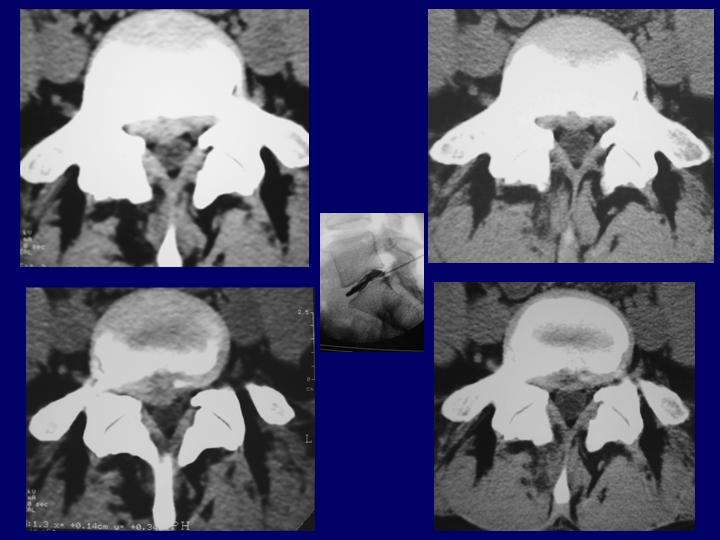

Hernias Discales